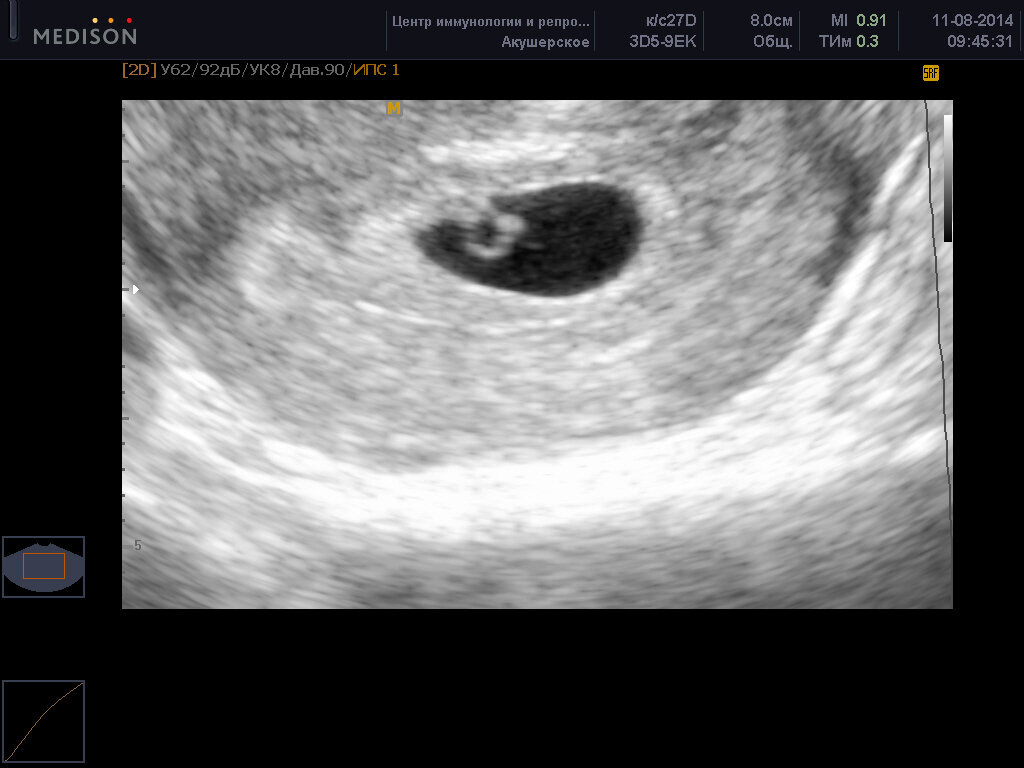

Дни между тем шли один за другим. Ничего не происходило. На восьмой неделе я записалась на УЗИ.

Там я узнала, что беременность маточная и развивается хорошо. Есть эмбрион и сердцебиение - "+". Врач показала мне на экране маленькую сокращающуюся точку - бьющееся сердце.